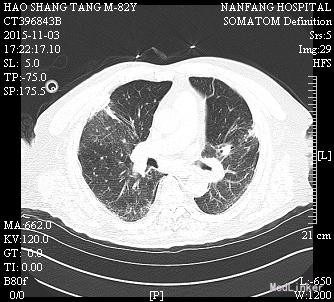

男,82岁,已婚,因“肢体抽搐伴意识障碍1天“入我院神经内科,因肺部感染加重10天后转入呼吸内科

入神经内科经舒普深抗感染及抗癫痫等治疗,无明显癫痫,但肺部感染加重,查见广泛耐药鲍曼不动杆菌及铜绿假单胞菌感染,转入呼吸科后给予美平联合舒普深治疗,1周后成功拔管脱机,2周后体温完全正常,转入康复科继续治疗